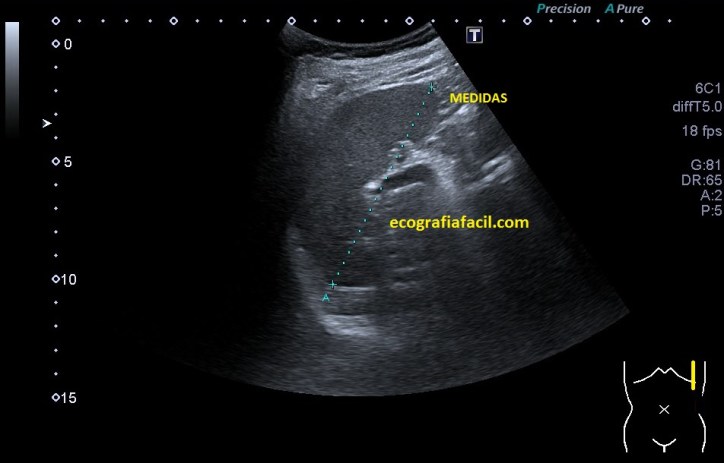

Además de una vejiga suficientemente repleccionada, necesitamos esquivar el Pubis, anterior a la Próstata, para eso tendremos que realizar una angulación, que estará en función de cada paciente, para poder acceder a la glándula correctamente tanto en transverso como en longitudinal, que son los dos planos que necesitamos para hacer la medida de la Próstata en los tres ejes de espacio para obtener un volumen de la estructura.

Para llegar a ver la Próstata, con el paciente debidamente preparado, vamos a localizar un corte transverso de la Vejiga y cuando la veamos, realizaremos la angulación arriba mencionada para llegar a la Próstata, este paso es el más complicado técnicamente, pero aquí reside el éxito de la exploración, mira, he hecho un dibujo para explicarlo:

Con angulación caudal.

Resultado.

Perfecto, ahora que ya tenemos localizada la estructura hay que realizar dos cortes, transverso y longitudinal, de dicha glándula y haremos fotos de aquellos que lógicamente nos representen en la imagen la Próstata en su máximo tamaño, es decir, cortes centrales, no nos valen cortes periféricos de la estructura, ojo que en algunos pacientes, ésta será grande, pero en otros, será más pequeña y eso nos puede dificultar nuestra labor y tendremos que ser muy fino/as.

Los cortes serán estos:

Rojo: Transverso. Amarillo: Longitudinal SIEMPRE CON ANGULACIÓN.

El resultado será lo más parecido a esto:

En la imagen podemos ver, posterior a la Vejiga (anecoica), una estructura ovalada, hipoecogénica y homogénea, que es la Próstata, a la que le realizamos tres medidas para obtener un volumen:

• Derecha-Izquierda (Corte Transverso)

• Antero-Posterior (Corte Transverso)

• Cráneo-Caudal (Corte Longitudinal)

Estos tres cortes son indispensables para conseguir el volumen de la estructura, que previamente, en nuestro menú, habremos activado entrando en MEDIDAS y seleccionando la opción de VOLUMEN, que en cada casa comercial, será de una manera determinada.

Medidas y Volumen en cm3.